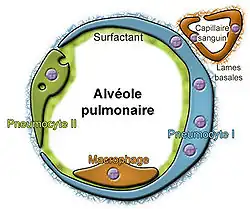

C'est dans les alvéoles, petits sacs terminant les voies ventilatoires, appelés sacs pulmonaires ou vésicules pulmonaires, que se produisent les échanges gazeux. Ces alvéoles sont tapissées d'une paroi très fine (jusqu'à 0,2 μm ; pour comparaison, le diamètre des globules rouges est de 7 μm) contenant les capillaires. La surface totale destinée aux échanges est d'environ 140 m2[5] soit la taille d'un terrain de volley. Ceci permet aux alvéoles d'assurer leur rôle, qui est de transmettre l'oxygène au sang et d'en extraire le dioxyde de carbone.

Avant d'arriver dans les alvéoles, l'air inhalé a été réchauffé, humidifié et purifié par le mucus qui tapisse les voies ventilatoires. Il a emprunté des canaux qui se sont subdivisés (arborescence pulmonaire) 20 à 25 fois entre la trachée et les alvéoles[6]. Cet air est passé de la zone nasale à la grande surface développée des alvéoles, où les échanges gazeux peuvent se faire. Les organismes ont développé de puissants mécanismes de défense innée qui protègent et régénèrent en permanence les voies ventilatoires contre la plupart des bactéries, particules et virus y pénétrant. Ces mécanismes qui impliquent presque tout le mucus pulmonaire restent néanmoins sans effet, ou sont moins efficaces contre certains contaminants (radionucléides, fibres d'amiante, nanoparticules, ou toxiques respiratoires tels que lacrymogènes et produits utilisés dans les armes chimiques de la Première Guerre mondiale)[réf. souhaitée].

Au dernier niveau, celui des alvéoles, des pneumocytes de type 2 sécrètent le surfactant pulmonaire. Ce dernier est essentiel, car il permet de diminuer la tension superficielle en limitant la distension pulmonaire. Pour comparaison, son rôle est le même que le savon qu'on ajoute à l'eau afin de former des bulles de savon. Il prévient le collapsus des alvéoles en phase d'expiration. Son immaturité chez le nouveau-né prématuré peut être responsable de la maladie des membranes hyalines.

Ce surfactant naturel est lavé par l'eau lors des noyades, ce qui impose une surveillance intensive des noyés réanimés.